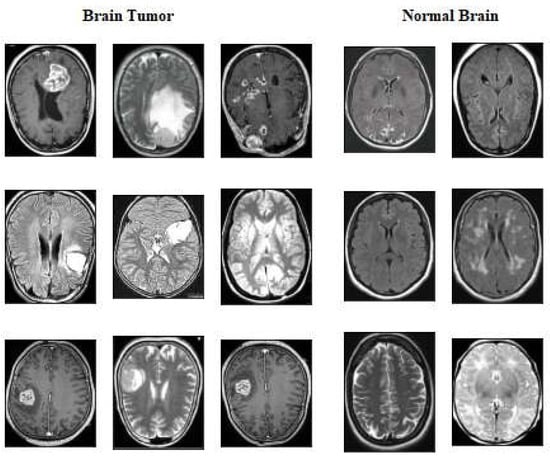

4.2. Dataset